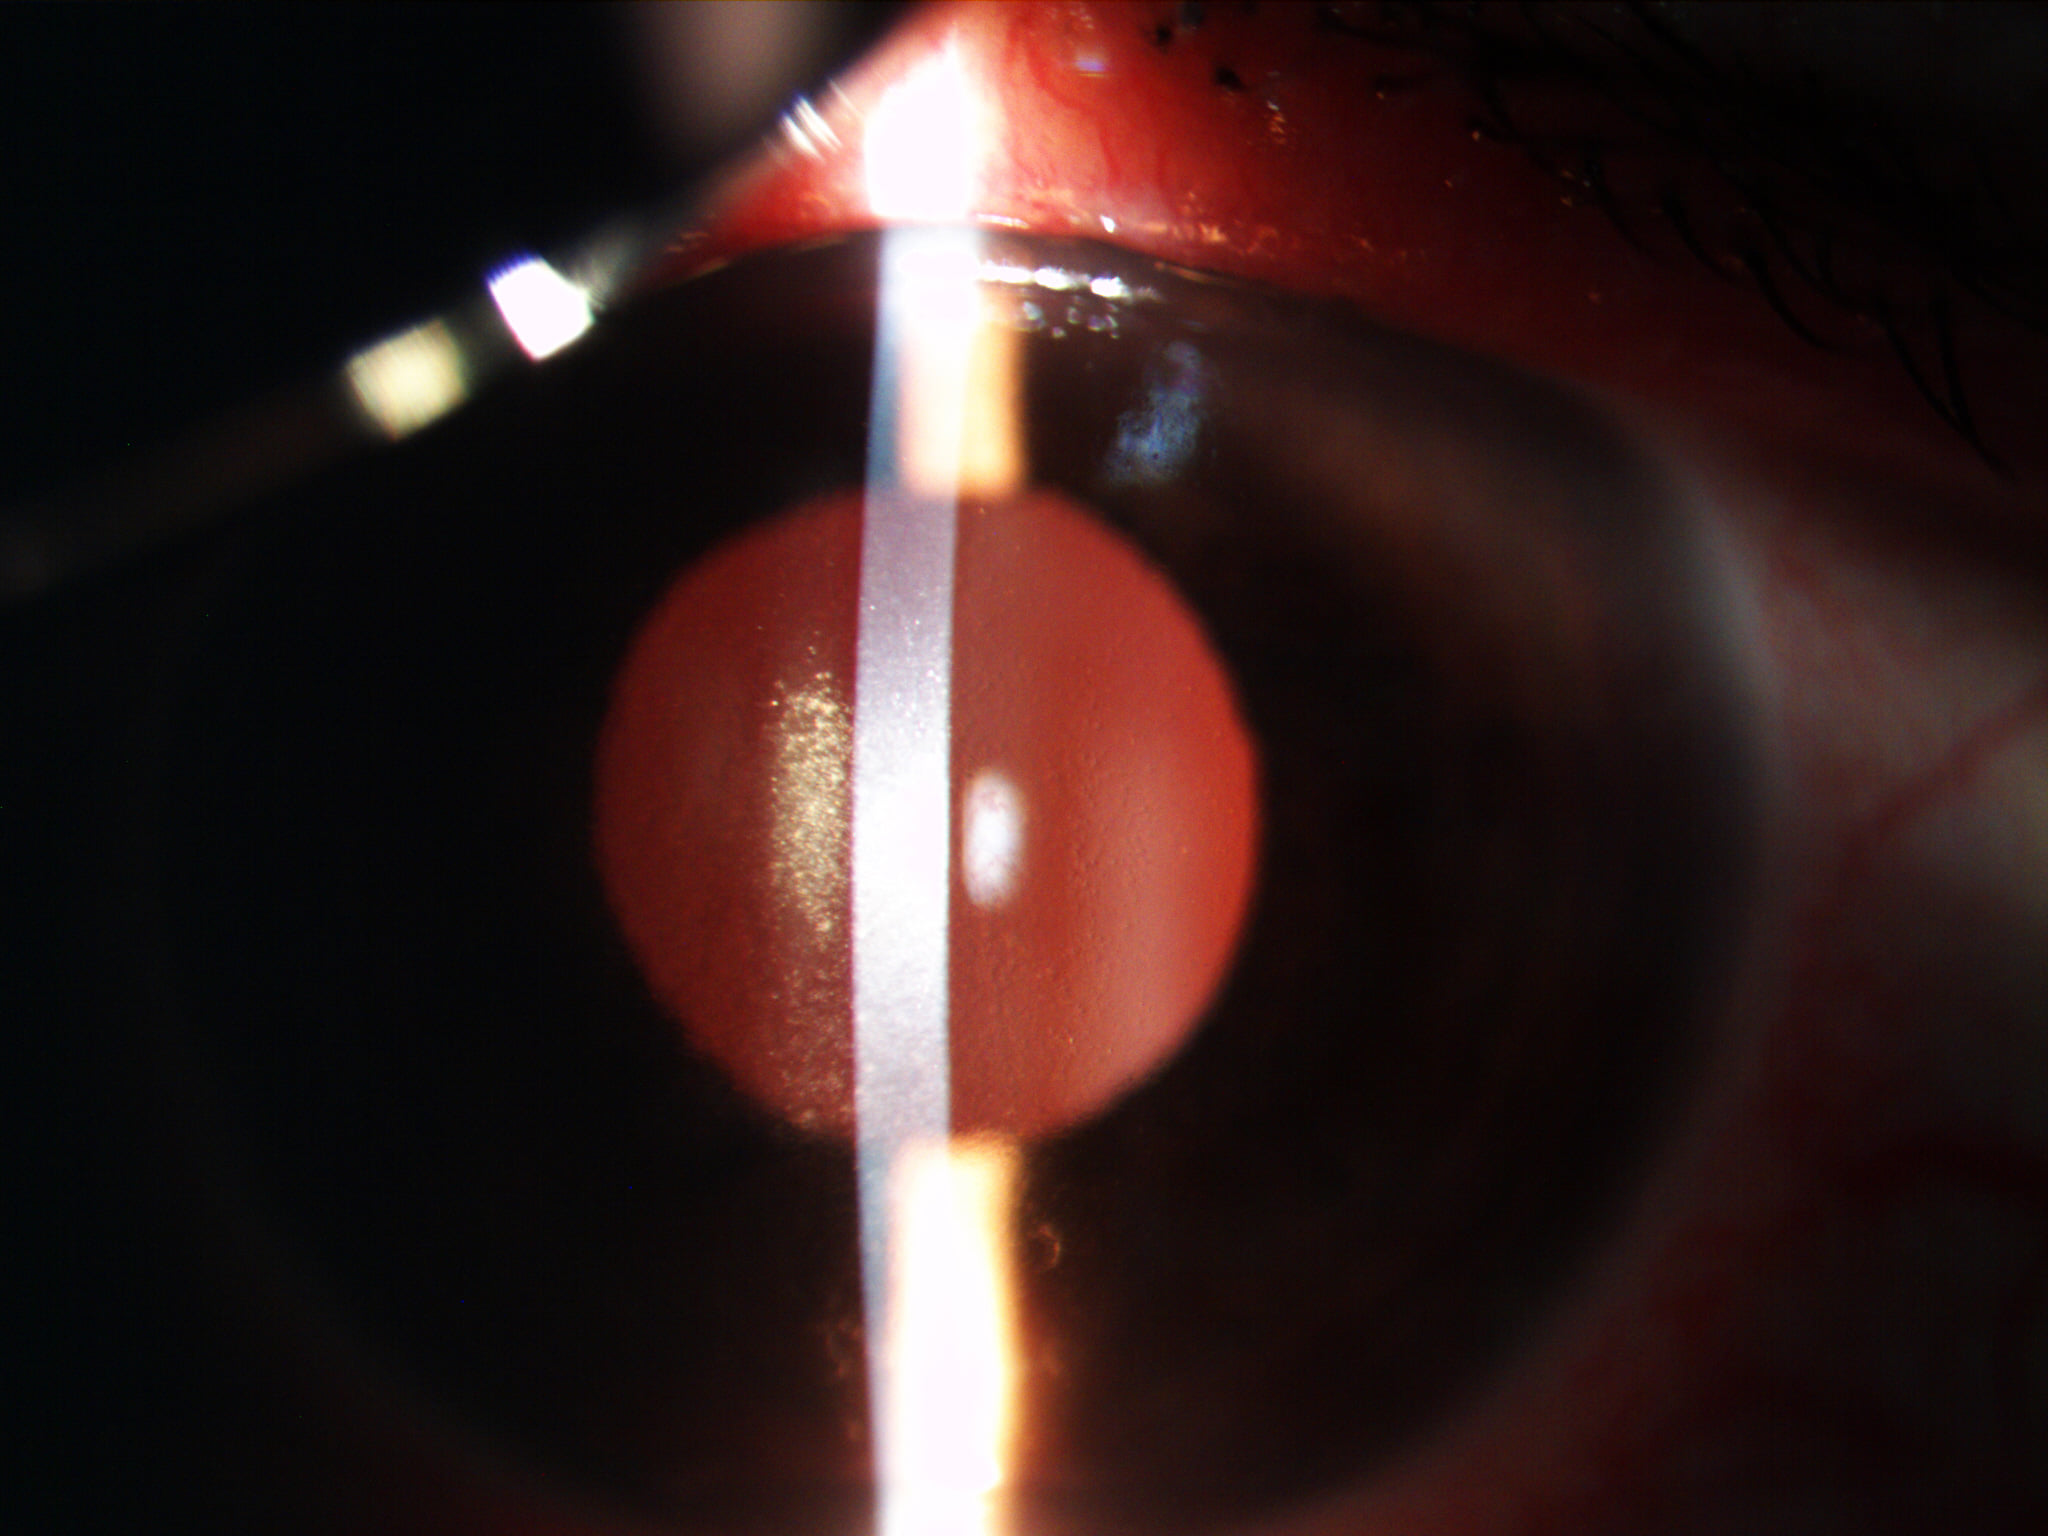

Mai jos, fotografii ale mai multor pacienti de-ai nostri cu Corneea Guttatta în faze medii, sau chiar avansate, la care am efectuat doar operația de cataractă, în urma căreia corneea a „supraviețuit” cu brio și nu a mai fost nevoie – cel puțin până acum – de un trasplant de cornee.